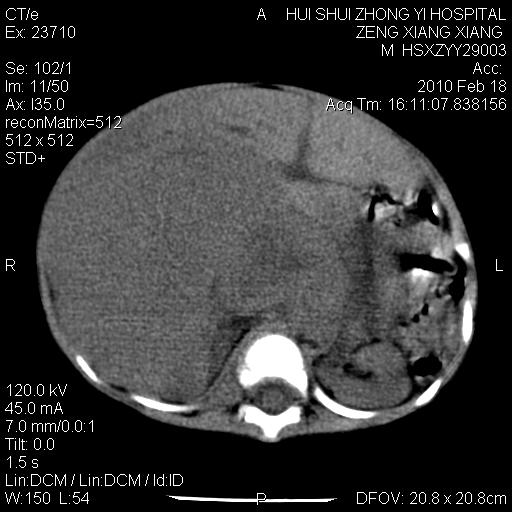

标题: PED3106:男,2岁,腹胀1月。 [打印本页]

标题: PED3106:男,2岁,腹胀1月。

定位腹膜后,肾上腺来源;

定性:恶性神经源性,肾上腺神经节母细胞瘤可能性大。

鉴别:肝母、肾母、肝脏中胚层错构瘤。

依据:年龄、有钙化,肾脏及肝脏受压移位。

肝母细胞瘤可能性大,右肾形态大体可见,不支持肾母细胞瘤,右肾移位不明显,肾上腺神经母细胞瘤可能性不大。